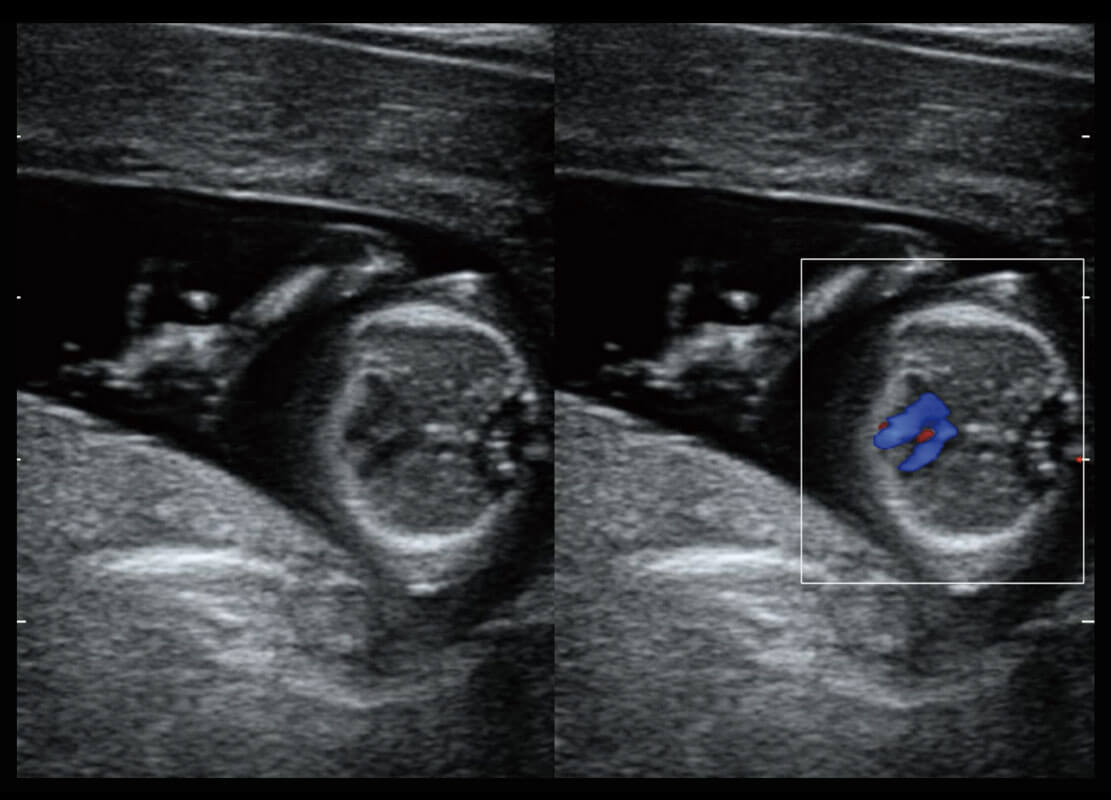

P60搭载一系列胎儿心脏成像技术,实现精细的胎儿心脏评估。

四腔切面